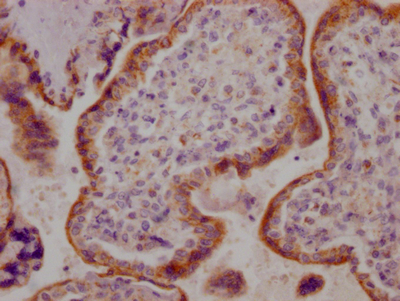

IHC image of CSB-RA260702A0HU diluted at 1:100 and staining in paraffin-embedded human breast cancer performed on a Leica BondTM system. After dewaxing and hydration, antigen retrieval was mediated by high pressure in a citrate buffer (pH 6.0). Section was blocked with 10% normal goat serum 30min at RT. Then primary antibody (1% BSA) was incubated at 4℃ overnight. The primary is detected by a Goat anti-rabbit IgG polymer labeled by HRP and visualized using 0.05% DAB.

IHC image of CSB-RA260702A0HU diluted at 1:100 and staining in paraffin-embedded human placenta tissue performed on a Leica BondTM system. After dewaxing and hydration, antigen retrieval was mediated by high pressure in a citrate buffer (pH 6.0). Section was blocked with 10% normal goat serum 30min at RT. Then primary antibody (1% BSA) was incubated at 4℃ overnight. The primary is detected by a Goat anti-rabbit IgG polymer labeled by HRP and visualized using 0.05% DAB.